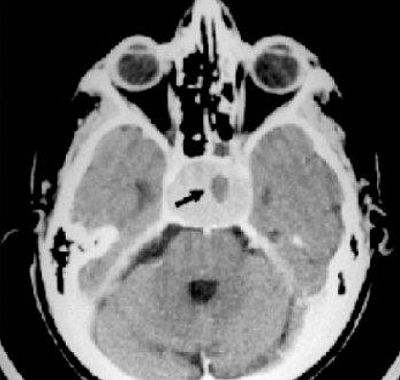

De hecho, durante esta extraña operación el médico alienígena raspaba el tejido parenquimático de la cavidad nasal, provocando una especie de fragilidad capilar, que puede ser la causa de estas pérdidas de sangre. Posteriormente, Hopkins y yo pudimos constatar, a través de la Tomografía Axial Computarizada, la presencia, en la hipófisis, de una mancha oscura de unos tres milímetros que algunos secuestrados tenían ... desde siempre.

No se trataba un tumor, porque este es, por lo general, mucho más grande, cuando se encuentra, y aparece, sin embargo, de color más claro, como se puede ver en esta radiografía.

Radiografía de un tumor, que por lo general aparece mucho más grande y de color más claro que los implantes alienígenas.